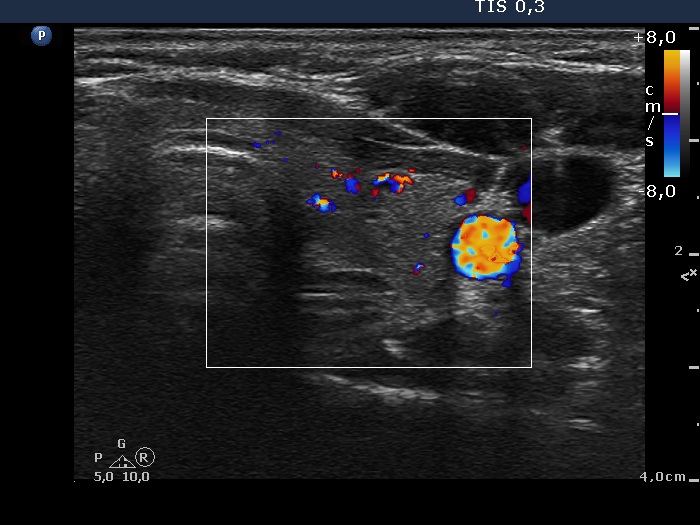

Subacute granulomatous thyroiditis - case 374

3 months after initial investigation (ultrasonographic picture 6)

Left lobe, transverse scan, color Doppler method. The vascularization is average.